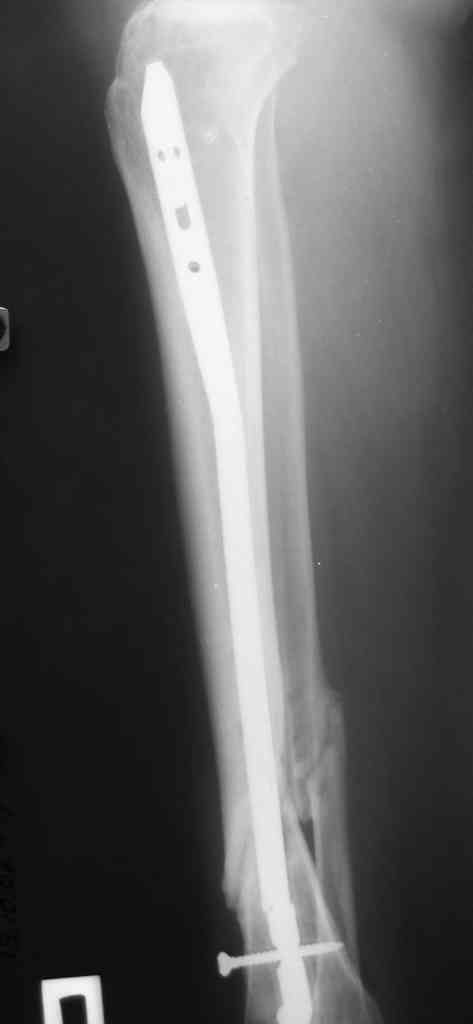

[Ortho] Ложный сустав голени перелом штифта

Р-граммы по теме прилагаю

Имя     : В.jpg